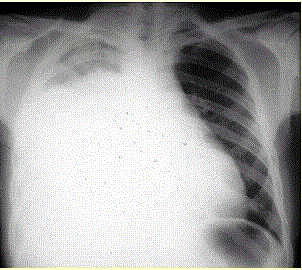

问题 患者男,34岁。进行性胸闷、气促1个月余,伴有干咳、右胸隐痛以及消瘦,无咯血、发热、盗汗、潮热等。(提示 胸部X线检查如图所示。) 该患者的初步诊断是

选项 A.右侧大量胸腔积液 B.右侧气胸 C.右侧肺不张 D.右侧液气胸 E.右侧大叶性肺炎 F.肺血栓栓塞症 G.右侧气胸

答案 A